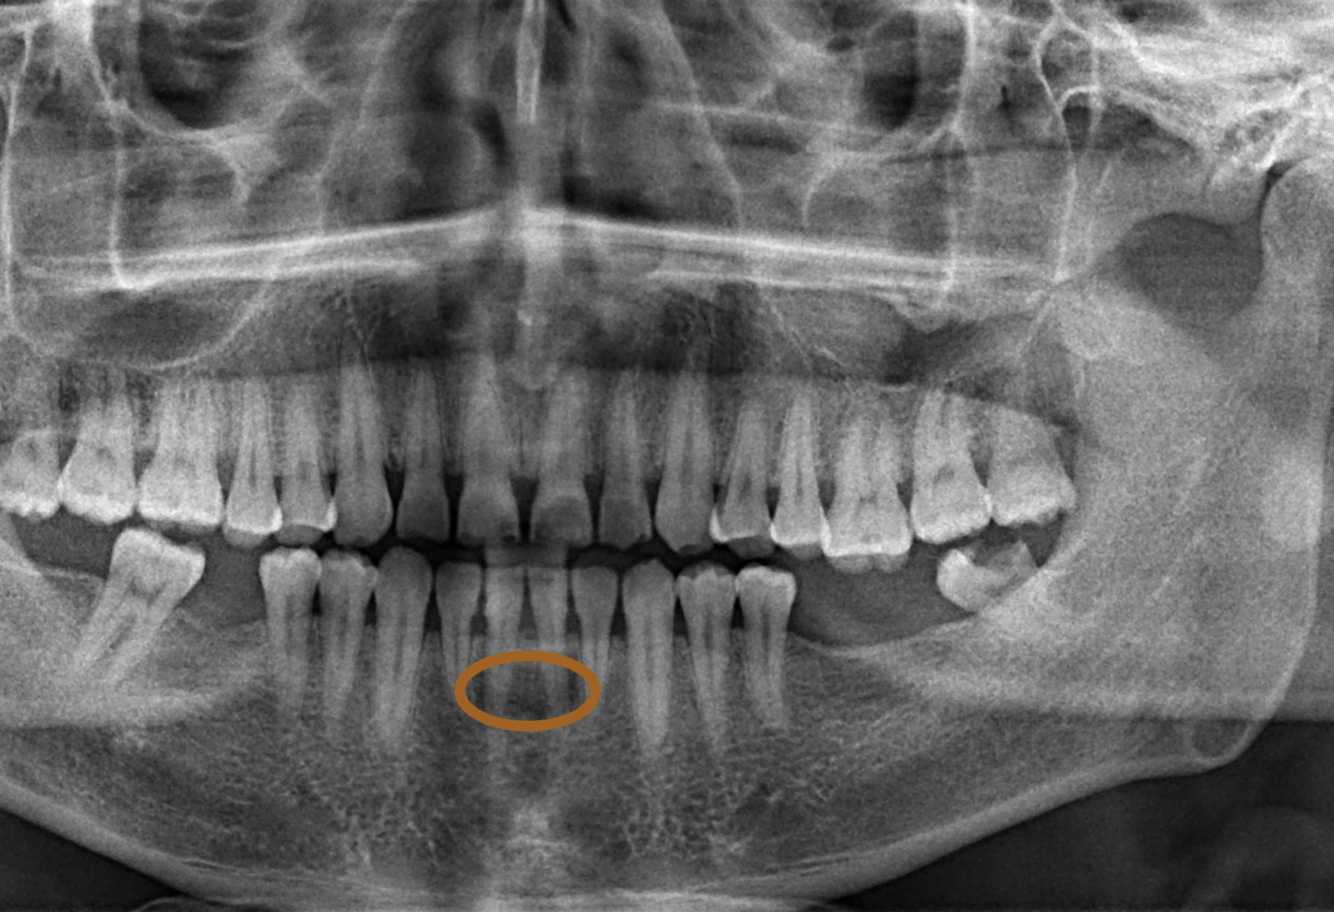

Q

What is represented by orange in the following image?

A

Inferior alveolar canal